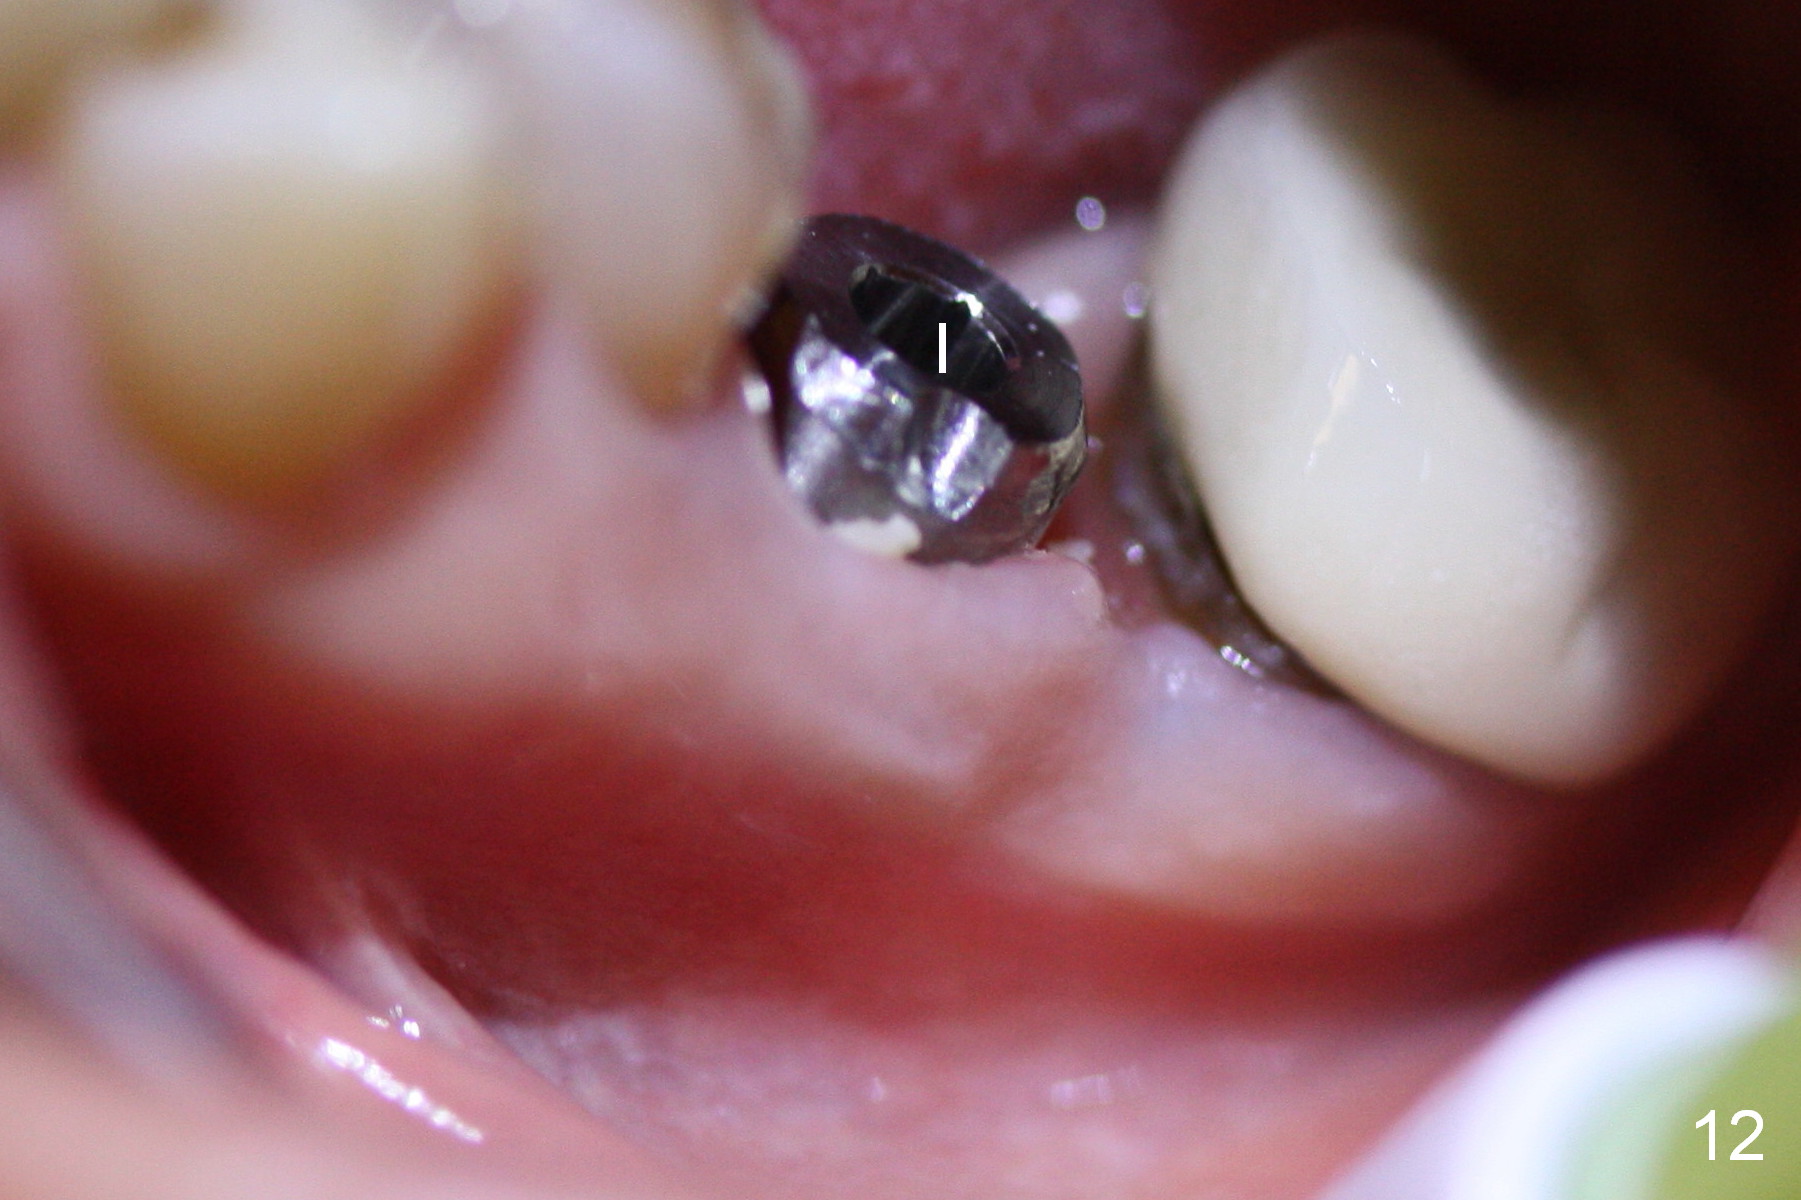

The patient returns for provisional recementation 1.5 months postop. The gingiva remains infection free (Fig.12), but the socket at the implant site has shrunk as compared to the 2nd molar site (Fig.13 arrowheads). Therefore, an implant should be placed before the socket shrinks post extraction, especially with preop lesion. Socket preservation does not prevent socket collapse. The implant is the best framework (tenting) for bone regrowth.